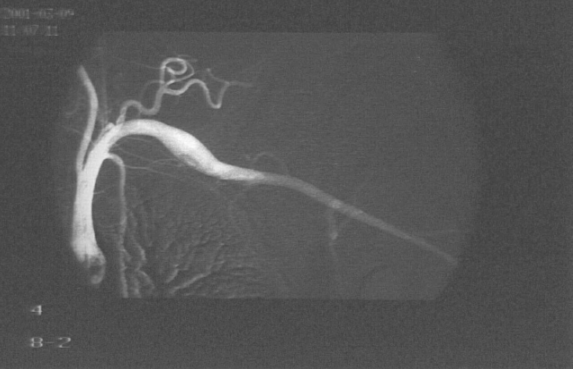

A 26-year-old left-handed healthy man presented with a three month history of repeated bilateral chest pain. Six months previously, he started heavy muscular activity of upper limbs (work out at a gym). Two months before he had been examined by his pulmonologist because chest X-ray revealed bilateral small effusion and tuberculin test had been positive. The patient started treatment as suspected tuberculous pleuritis and beside antituberculous drugs he used corticoids too. Despite treatment, difficulties remained and the patient was remitted to our clinic. On examination, there was no edema of the left arm, only prominent superficial veins on arm and left part of chest. On auscultation of the lungs, breath sounds were weakened bilaterally. Chest radiography revealed small pleural effusion. Electrocardiography and echocardiography were normal. Suspected pulmonary embolism was confirmed by computed tomography. DVT in lower limb was excluded by compression ultrasonography. Because the patient had prominent superficial veins on arm and left part of chest, we suspected left subclavian vein thrombosis, which was established by venography (Figure 1). Aortography revealed aneurysm of left subclavian artery (Figure 2) and also confirmed left thoracic outlet syndrome due to adherent first and second ribs (Figure 3), interruption of flow in left subclavian artery in abduction of left upper limb and appropriate flow in left subclavian artery in adduction of left upper limb (Figure 4). Patient was administered low molecular weight heparin as initial step, followed by the acenocoumarol therapy. A thrombophilia screen revealed prothrombin 20210A mutation, which was detected by polymerase chain reaction.

Figure 4: Aortography showed appropriate flow in left subclavian artery in adduction of left upper limb.